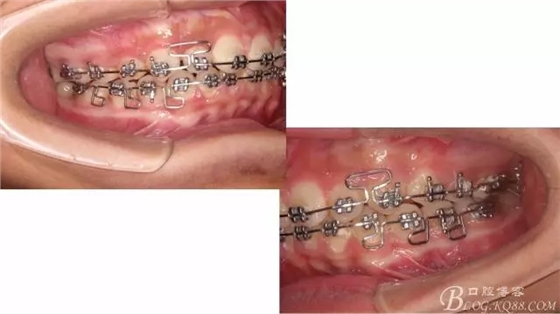

接下來盡管配合些雙側后牙對角牽引,咬合關系依,不盡人意。

下頜配合多曲方絲,三角牽引,調整咬合。